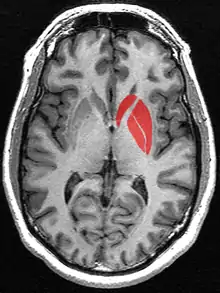

![]() | |

The striatum (pl.: striata), or corpus striatum[5] (also called the striate nucleus), is a nucleus (a cluster of neurons) in the subcortical basal ganglia of the forebrain. The striatum is a critical component of the motor and reward systems; receives glutamatergic and dopaminergic inputs from different sources; and serves as the primary input to the rest of the basal ganglia.

In primates, the striatum is divided into a ventral striatum, and a dorsal striatum, subdivisions that are based upon function and connections. The ventral striatum consists of the nucleus accumbens and the olfactory tubercle. The dorsal striatum consists of the caudate nucleus and the putamen. A white matter, nerve tract (the internal capsule) in the dorsal striatum separates the caudate nucleus and the putamen.[4] Anatomically, the term striatum describes its striped (striated) appearance of grey-and-white matter.[10]